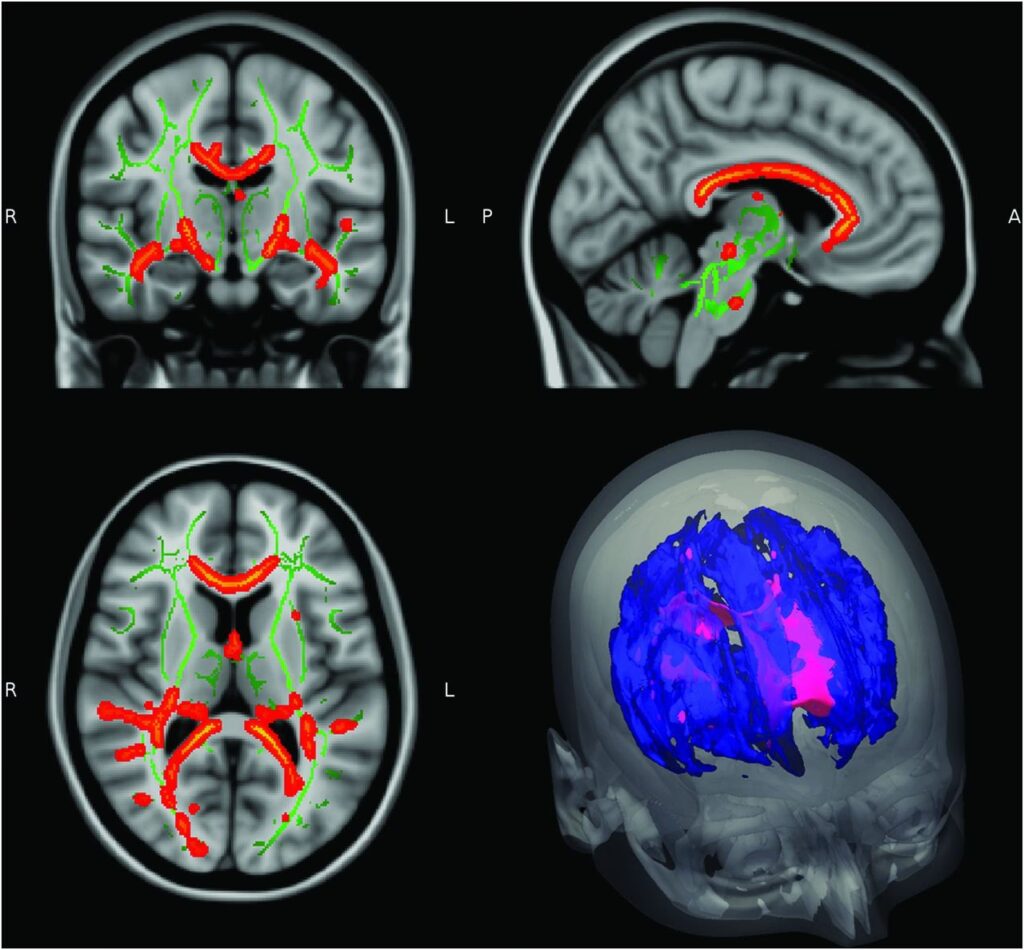

- Hjerneskanninger: Begge tilstande kan forårsage læsioner i hjernen, der kan se ens ud på en MR-skanning.

| Hjernelæsioner (MRI) | Ovale læsioner, ofte periventrikulære (nær væskefyldte hulrum) | Punktformede læsioner, kan involvere basal-ganglier |